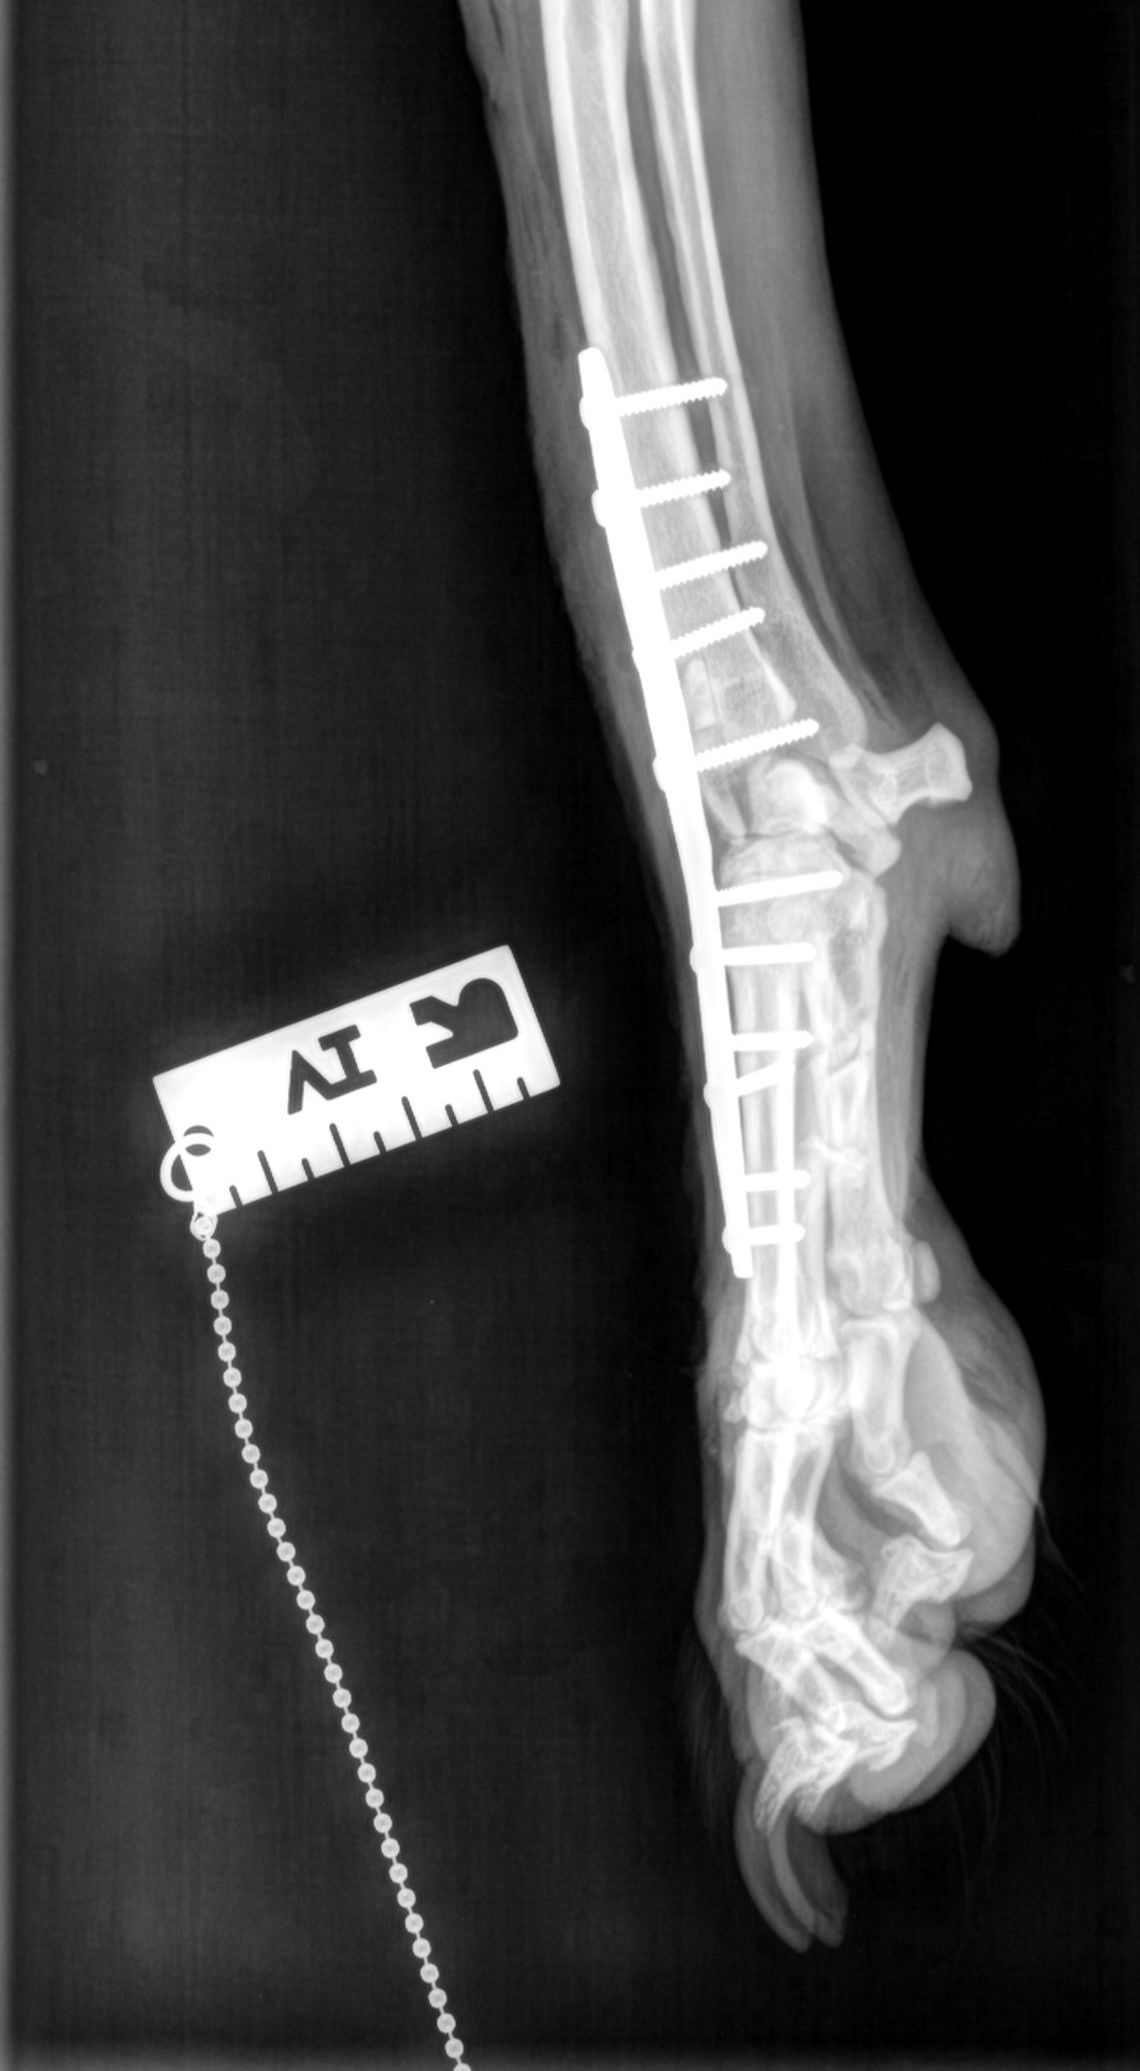

- Breites chirurgisches Spektrum innerhalb der Weichteilchirurgie, der orthopädischen Chirurgie, Neurochirurgie, Thoraxchirurgie u.a. chirurgische Fachgebiete